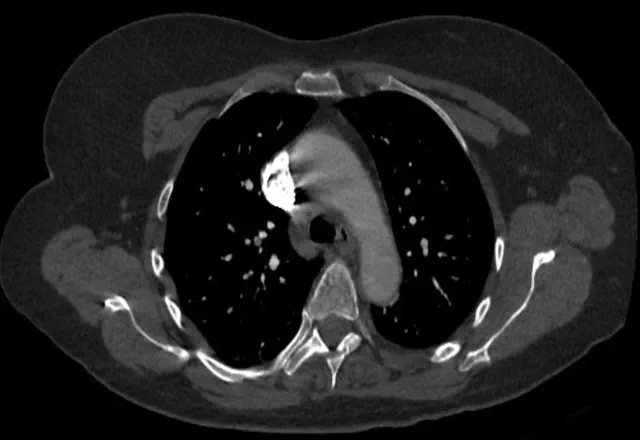

Subsegmental pulmonary embolism are both small and peripheral. Patients can be symptomatic or not. The small size of these emboli result in important management questions. Mainly, should we even treat pulmonary embolism that are very distal and very small? Some argue that we are simply finding more clots that don’t mean much, because of improved imaging. They argue that these are probably not clinically relevant. But there are some data that point to poor patient outcomes, comparable to more proximal pulmonary emboli.

Subsegmental pulmonary embolism is a modern diagnosis. It was not relevant before the mid 1990’s. An epidemiological study examined the prevalence of pulmonary embolism before and after multi-detector CT became available. Obviously, the results showed that CT detected pulmonary embolism more commonly. However, this did not affect mortality. In other words, CT detected more insignificant pulmonary emboli. These emboli were most commonly subsegmental pulmonary embolism. Over the same time period there were more treatment related complications. More patients who were receiving anticoagulation for the treatment of pulmonary embolism actually bled.

Furthermore, random autopsies, report otherwise unknown small and peripheral clots in patients with deep vein thrombosis and in patients undergoing CT for other reasons. Many of these emboli were not found previously when ventilation-perfusion scans were the main method for the diagnosis of pulmonary emboli.

A meta-analysis examined prospective studies of symptomatic subsegmental pulmonary emboli. Subsegmental pulmonary embolism was detected in as many as 9.4% of patients suspected of having a pulmonary embolism. The rate was higher with multiple detector CT compared to single-detector CT. All patients in the included studies who were diagnosed with a thrombotic event were treated with anticoagulation. The 3-month rate of subsequent venous thromboembolism was then examined among patients that had a negative first scan. The rate was the same for multi-detector CT and for single-detector CT. From this the authors concluded that subsegmental PE’s detected by multi-detector CT are not clinically significant and do not necessarily need to be treated.